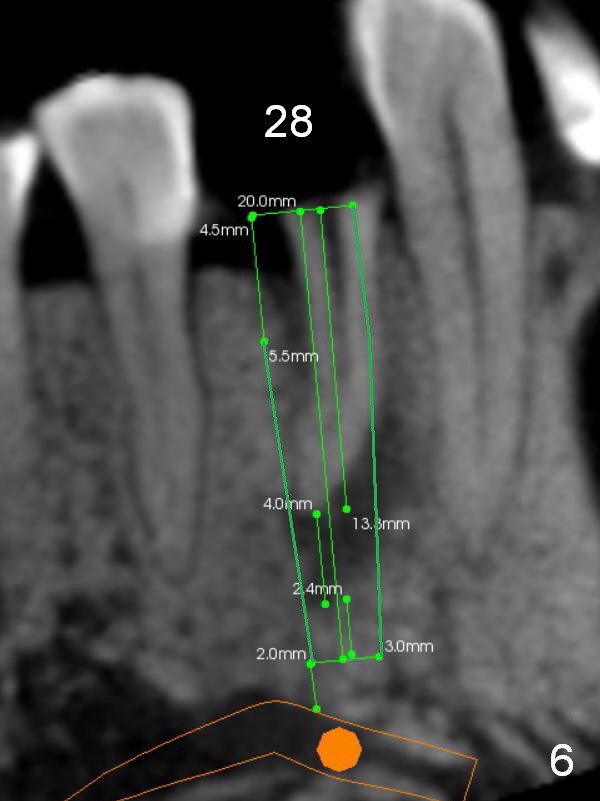

CT sagittal section shows that it is possible to place 4.5x20 mm implant (Fig.6). Axial (Fig.7) and coronal (Fig.9) sections show that the lingual (L) plate is much thicker than the buccal (B) one. To prevent the implant being buccally deviated, a Lindermann bur is used after extraction (black area in Fig.8,10) to remove ~ 1mm bone from the lingual plate (red area in Fig.8,11). A 2 mm pilot drill is placed as lingual as possible (green in Fig.8,11). If the implant (Fig.12) starts to deviate buccally while being placed, remove it from the osteotomy and remove more bone from the lingual plate. Place the implant again and monitor the trajectory tightly.